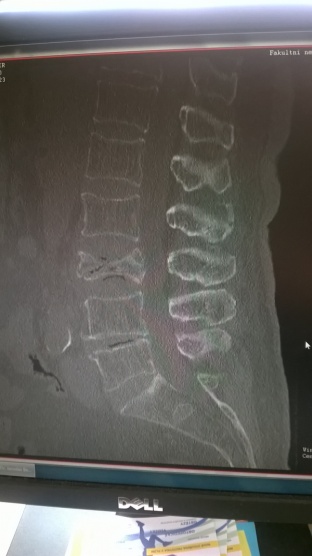

Zdravím, téměř v 70 letech jsem upadl v bezvedomí na rovné podlaze a výsledkem je zlomenina L3 bederního obratle. Po 4 měsících mi přetrvávají bolesti, které mi brání se zcela narovnat v bedrech, stát a dělat delší kroky. Za púár dnů mne čeká vyšetření mag. resonancí a pak naplánování operace, protože patrně nějaký úlomek vnikl do páteřního kanálu. Bohužel ke spondylochirurgovi mne spádový ortoped neposlal, takže se obratel stále snižoval, až srostl. Shodou okolností můj spolužák je neurochirurgem ve Švýcarsku a odoperoval už přes 6 tis. páteří, Ten mi k fotkám z rentgenů a CT napsal, že u nich běžný postup je co nejdříve po úrazu obratel roztáhnout a stabilizovat vstříknutím cementu s následným zpevněním cementem i sousedních obratlů.Prý pak pacient může v podstatě ihned zase normálně fungovat. Už se to prý praktikuje 15 let. Nechápu pak, proč jsem tenhle způsob nezahlédl v žádné diskuzi k tématu. To se u nás opravdu přešlo jen od sádrového lůžka k titanovým šroubům?

WP_20141023_13_42_02.jpg